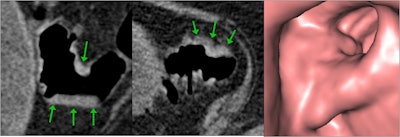

When performed to the highest quality, CTC has excellent diagnostic accuracy for clinically significant neoplasia -- i.e., colorectal cancer and advanced neoplasia -- in both symptomatic and screening populations. But unlike colonoscopy, substantial variations in practice exist in the U.K. and internationally, they added.

- Technical and process standards ("what to do")

The guidance uses all available evidence to define optimum examination technique and standards of reporting including both minimum numbers of examinations to be reported by an individual and the time taken to report studies. "These are the performance indicators which allow us to evaluate our own departments and individual performance," he said.